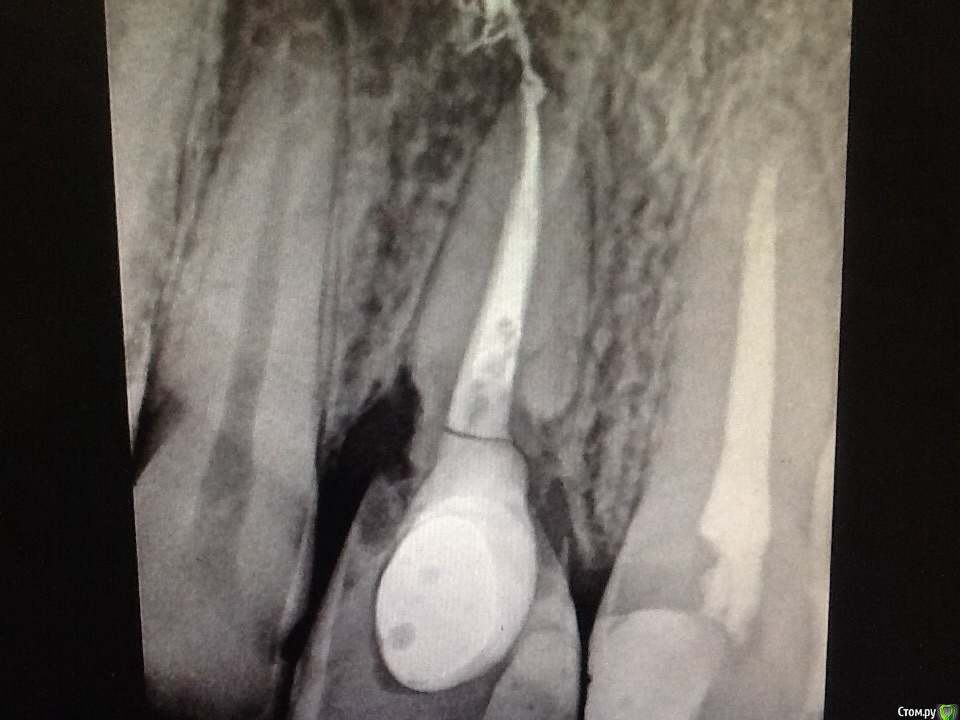

Л Ю С Я Опубликовано 10 сентября, 2015 Поделиться Опубликовано 10 сентября, 2015 ,почему то про резорбцию ни кто не пишет,а осложнение серьёзное! Чегойто не пишет, сто раз говорено. А вот, собственно, и оно: Ссылка на комментарий

domino Опубликовано 18 ноября, 2015 Поделиться Опубликовано 18 ноября, 2015 А почему такое получилось?Плохо отмыли отбел или плохо загерметизировали?Тогда почему резорбция латерально, там как герметизировать? Ссылка на комментарий

St. Опубликовано 19 ноября, 2015 Поделиться Опубликовано 19 ноября, 2015 Отбел можно наносить только в коронковой части, до эмалево-цементной границы и обязательно герметизировать подлежащую гутту. если попадет ниже - может быть резорбция. Ссылка на комментарий

Л Ю С Я Опубликовано 19 ноября, 2015 Поделиться Опубликовано 19 ноября, 2015 А почему такое получилось?Плохо отмыли отбел или плохо загерметизировали?Тогда почему резорбция латерально, там как герметизировать?Плохая устьевая пробка, негерметичность , пробка ниже уровня цэ границы. Механизм возникновения:остеокласты ниже эпителиального прикрепления способны пожирать дентин зуба, Михаил Соломонов хорошо об этом рассказывает на своих лекциях Ссылка на комментарий

ARislanV Опубликовано 29 ноября, 2015 Поделиться Опубликовано 29 ноября, 2015 Вроде тоже слышал, что отбеливатель должен находиться выше уровня десны и потом еще вроде перед постоянной реставрацией кальций оставляют. Для восстановления PH и видимо для профилактики резорбции. Ссылка на комментарий